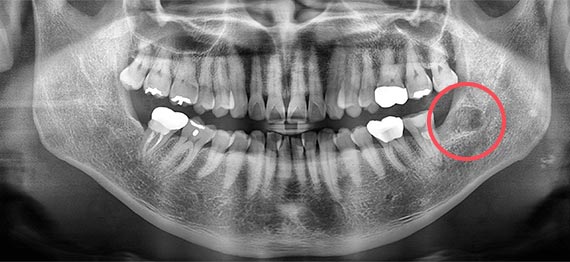

아래 사랑니의 경우 큰 턱뼈신경과 겹쳐져 있을 때는 일시적으로 아래 턱에 신경 감각이상을 유발할 수 있으나 약을 드시면 회복할 수 있습니다. |